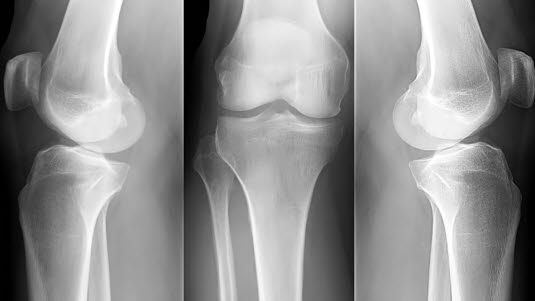

Beinvev framstilles tydelig på røntgenbilder. Bløtvevet rundt beinvevet framstilles som skygger av varierende tetthet, mens hevelser og forkalkninger kan ses på røntgen. Brusk, leddbånd og sener lar seg ikke fremstille direkte på røntgen.

Gode røntgenbilder forutsetter at området som avbildes holdes i ro. Som regel er det nødvendig å ta bilder fra minst to retninger for å få en tilfredsstillende fremstilling av beinet. Vanligvis tas disse vinkelrett på hverandre - vanligvis forfra/bak og sidebilde (jfr. albue front og albue side nedenfor). Mer detaljert informasjon om et bein vil kunne kreve flere projeksjoner, f.eks. skråbilder.